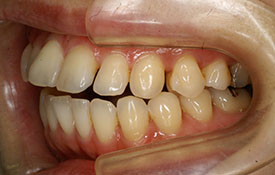

インビザラインの治療例:CASE-2

| プロフィール | 15歳 男性 |

| 所見 | アメリカから転院されて来られた方です。 インビザラインで上下顎の矯正治療を開始し下顎はアメリカで終了しており、上顎のみ治療の後期を担当しました。 アイライナーの装着は、1日平均22時間ほどでした。 |